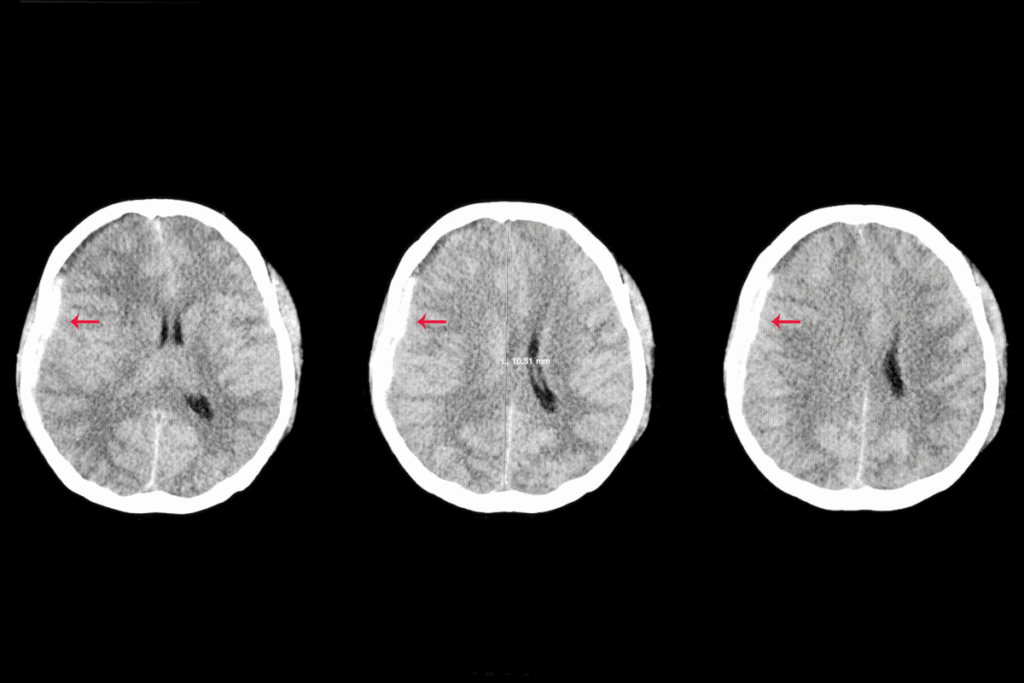

Symptoms and Diagnosis

Diagnosis usually involves imaging tests like CT scans, MRI, or cerebral angiography. These tests help visualize the aneurysm and assess its size and location.